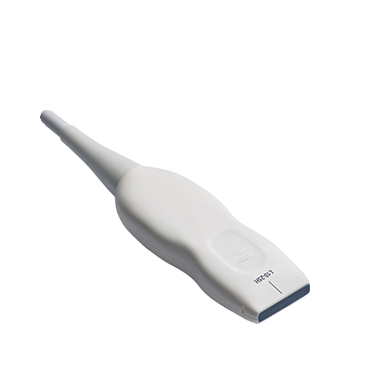

3-19 MHz 一體成型超寬頻探頭

10-25 MHz 超高頻探頭